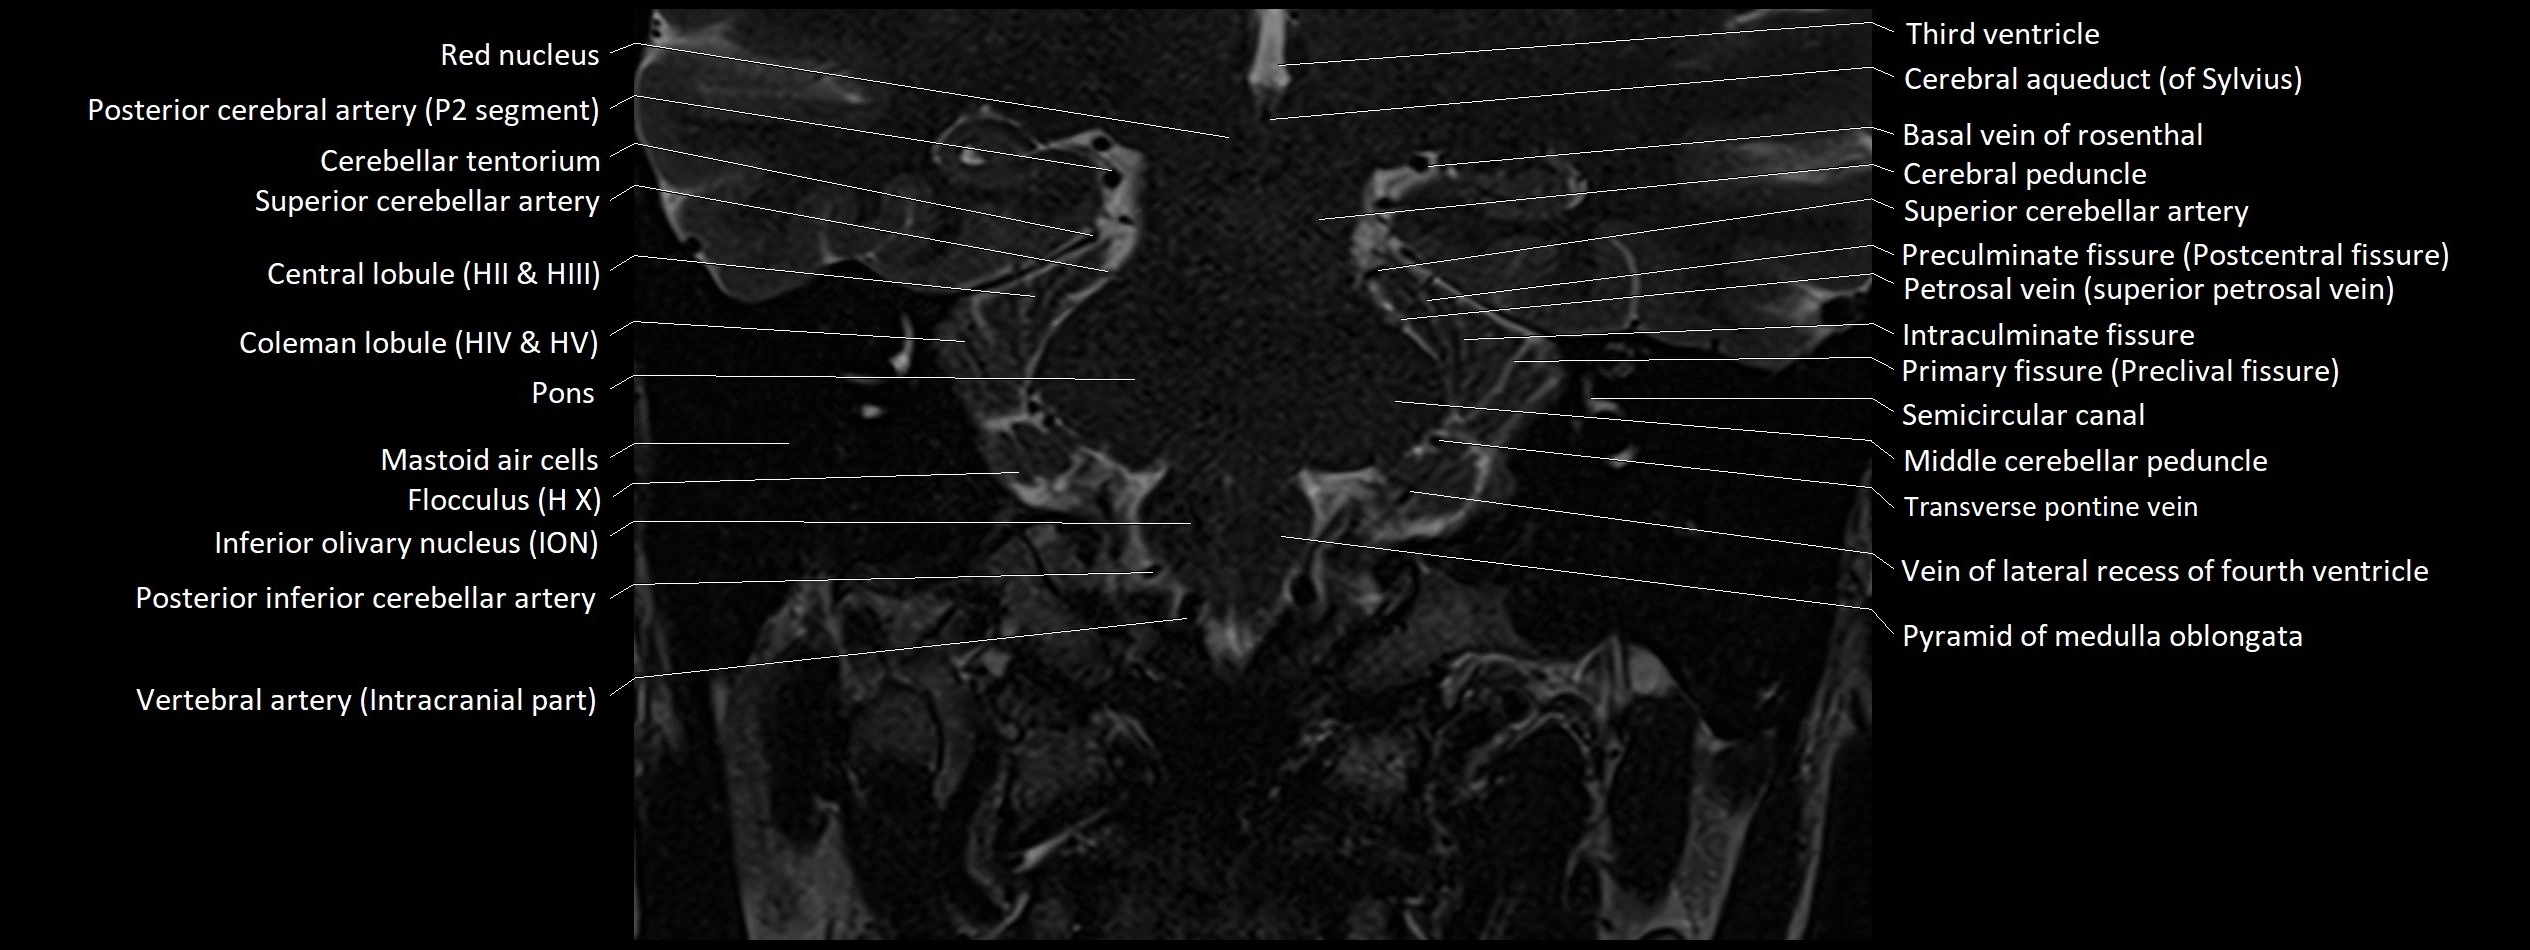

MRI images